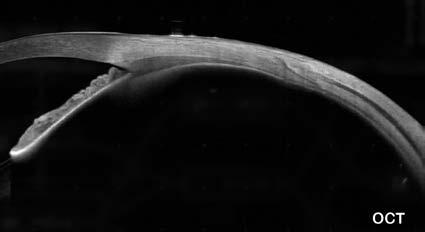

La cirugía refractiva está experimentado un cambio con el incremento de la realización de implantes de lentes fáquicas de cámara posterior. Resultan una alternativa válida a la cirugía refractiva corneal debido a ventajas como reversibilidad, no afectar la estructura corneal y ausencia de problemas de ojo seco. Sin embargo, la correcta selección preoperatoria y el seguimiento postoperatorio son cruciales para evitar complicaciones como la formación de cataratas. La ultrabiomicroscopía ultrasónica (UBM) es fundamental para evaluar la anatomía del sulcus ciliar y detectar quistes, que pueden surgir de forma secundaria o primaria. Aunque la presencia de quistes no contraindica totalmente la cirugía, es esencial evaluar su número, ubicación y tamaño. Estudios recientes muestran alta prevalencia de quistes, destacando que esto influirá en la selección del tipo y tamaño de la lente para evitar complicaciones como vaults elevados y rotación de lentes tóricas.

La ultrabiomicroscopía ultrasónica (UBM) resulta ser el método de diagnóstico por imágenes más adecuado para evaluar la anatomía del sulcus ciliar y poder detectar alteraciones anatómicas como pueden ser los quistes.5 Los quistes pueden aparecer de forma secundaria por ejemplo en casos de antecedentes de traumas, aunque también existen los quistes primarios.6 Determinar la existencia o no de quistes en la evaluación preoperatoria de un paciente en quien se desee realizar el implante de una lentes fáquica de cámara posterior es importante, porque como veremos más adelante, en algunos casos se pueden producir problemas potencialmente severos, aunque su sola presencia no es motivo de contraindicación absoluta, ya que habrá que considerar variables como su número, localización y tamaño. Por lo tanto, es importante la evaluación anatómica de esta región, mediante la UBM para detectarlos.7,8 Su correcta ponderación podrá ser de utilidad para evitar errores a la hora de efec-

Igualmente, en la actualidad la información existente en la literatura médica sobre el tema es escasa. En nuestro caso, se trata de un tema que venimos siguiendo y nos ha llamado la atención porque en un primer estudio dónde analizamos la presencia de quistes en 86 ojos de 43 pacientes que realizaron su evaluación preoperatoria de forma consecutiva, encontramos una muy alta prevalencia, cercana mayor al 47% (41 ojo tenían al menos un quiste)10 Pero en un estudio posterior que fuera recientemente publicado,11 se analizaron aspectos de seguridad y eficacia a cinco años en pacientes implantados con una lente fáquica denominada “IPCL” (Care Group, India) y aunque se encontró una llamativa prevalencia de presencia de quistes, fue menor a lo detectado en el estudio previo, donde de 140 ojos, 50 tuvieron quistes. Algo interesante a destacar, en relación a su repercusión clínica, es que al analizar el grupo de ojos con vaults mayores a 750 micras, encontramos una diferencia estadística-

mente significativa (p<0.001) para los ojos que tuvieron quistes, siendo por lo tanto los quistes, un factor de riesgo determinante para tener vaults elevados.